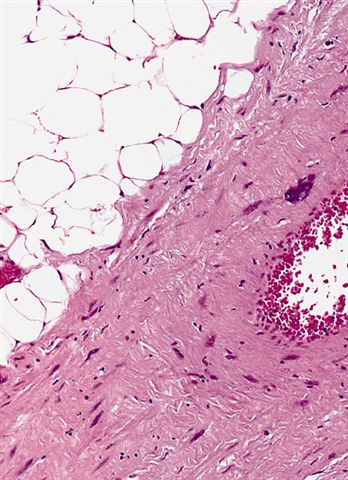

Microscopic (histologic) images

Contributed by Michael Clay, M.D., Melanie Bourgeau, M.D. and AFIP

Metaplastic change:

- Lipoleiomyosarcoma

- Liposarcoma with leiomyosarcomatous differentiation

- Both components are low grade

- Variable amount of the smooth muscle component, which can be seen in association with large vascular walls

- Similar biology and can dedifferentiate